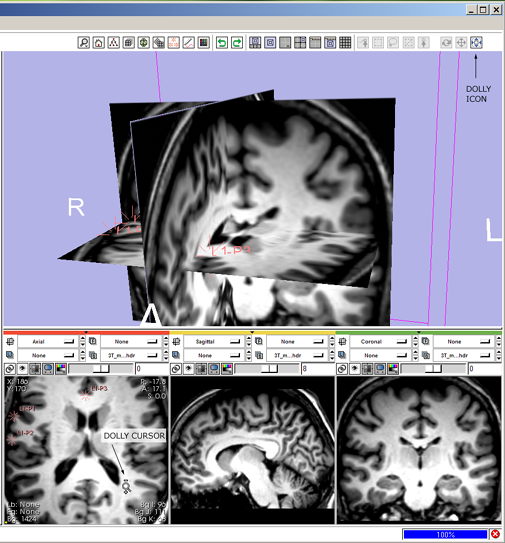

| + | 2(novice) '''dolly:''' click the view dolly mouse-mode icon [[image:ToolbarMouseZoom.png]] | ||

| + | * --> mouse-dolly icon hightlights and all others deselect, cursor changes to i ndicate mouse-dolly mode. | ||

| + | * then left-Click and drag in the 3D Viewer to dolly the camera in and out. | ||

| + | 2(expert) '''dolly:''' shift+left-Click and drag in the 3D Viewer | ||

| + | * --> mouse-dolly icon [[image:ToolbarMouseZoom.png]] highlights and all others deselect; cursor changes to indicate mouse-dolly mode; view zooms. | ||

| + | [[image:SB2.png]] | ||

2(novice) dolly: click the view dolly mouse-mode icon ![]()

- --> mouse-dolly icon hightlights and all others deselect, cursor changes to i ndicate mouse-dolly mode.

- then left-Click and drag in the 3D Viewer to dolly the camera in and out.

2(expert) dolly: shift+left-Click and drag in the 3D Viewer

- --> mouse-dolly icon

highlights and all others deselect; cursor changes to indicate mouse-dolly mode; view zooms.

highlights and all others deselect; cursor changes to indicate mouse-dolly mode; view zooms.